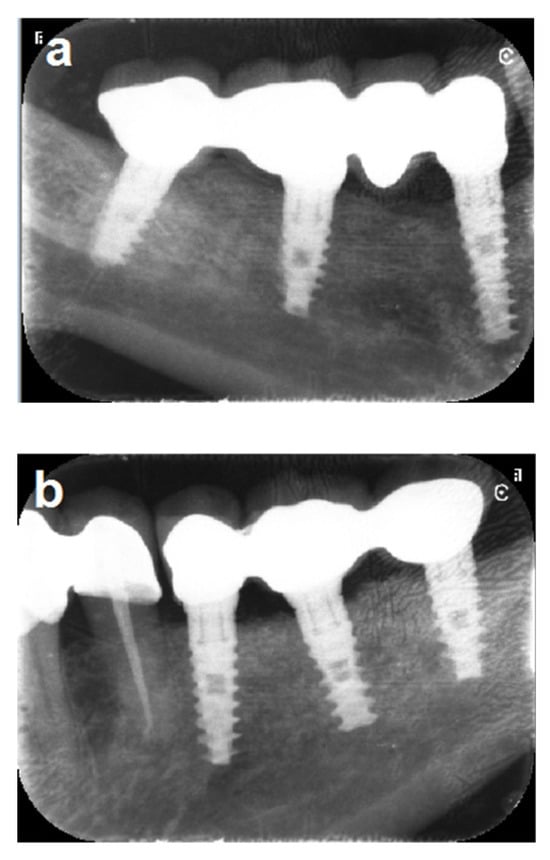

In one patient (Patient No. 19), one of three implants at the left mandibular site failed after 10 years. The failed implant was removed and replaced four months after particulate bone grafting, leading to successful fixed prosthetic rehabilitation with the remaining two implants. The same patient exhibited a 3 mm marginal bone loss on the right side (Figure 9). Another patient (Patient No. 6) experienced severe bone loss affecting the distal implant, along with a fracture of the mesial implant, after 13 years (Figure 10).

Figure 9.

(a,b) Ten-year follow-up periapical x-rays reveal severe bone loss involving the distal implant on the left side, along with 3 mm of marginal bone loss at the middle implant on the right side. (c–e) The images demonstrate stable bone grafts despite the severe marginal bone loss at the distal implant on the left side.